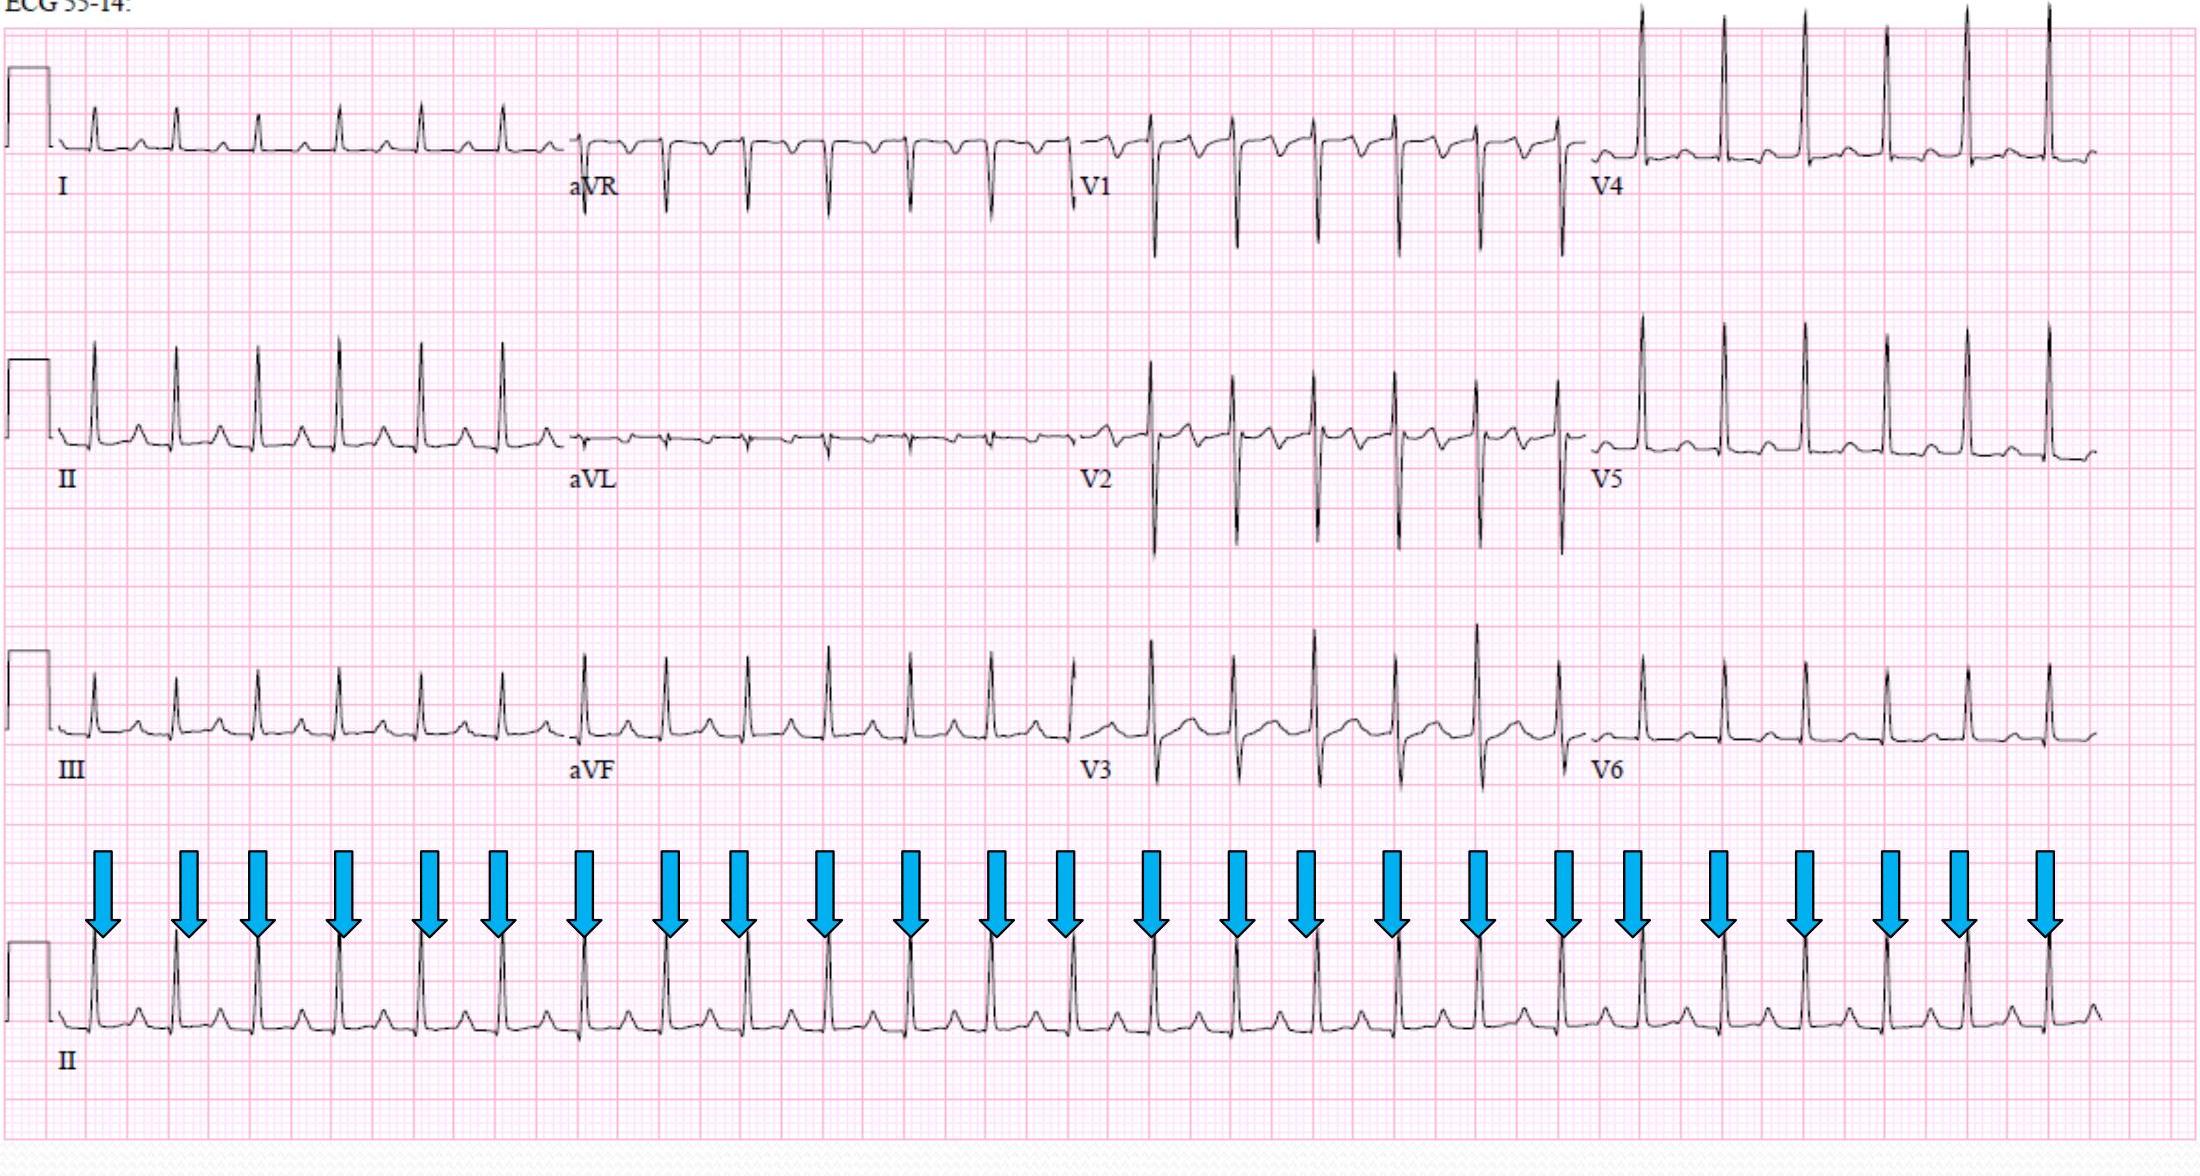

Premature Ventricular Contractions (PVCs) Y

Bigeminal Pattern

- 1:1

- no P wave

- wide QRS coming from ventricle

- “Regularly Irregular” Rhythm

- How to pick PVC clinically: Drop Pests